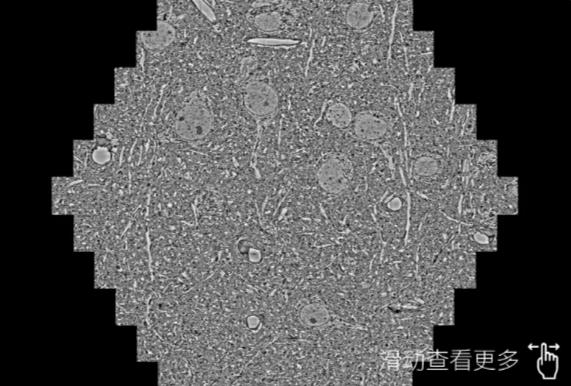

鼠脑切片。左图使用城口蔡司城口扫描电镜MultiSEM706对165μmx143pm面积区域成像,耗时仅需1.5秒。右图为鼠脑切片中30μm区域放大效果。样品由芝加哥大学B.Kasthuri提供。

使用蔡司高速城口扫描电镜MultiSEM对1mm²人脑皮层组织进行高分辨成像,并对其中的各种细胞结构进行三维重构分析。左图展示了2x3mm²组织平面中锥体神经元的三维重构效果。右图显示了局部体积神经元三维重构。图像由哈佛大学chtman实验室提供,渲染图由D. Berger 制作。